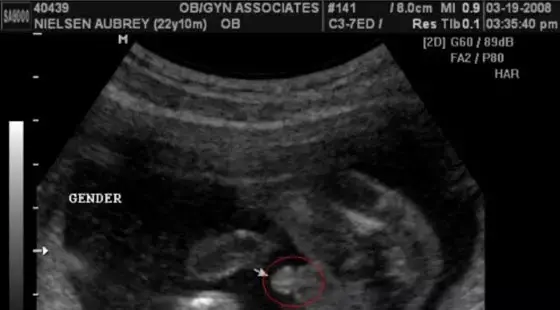

有人說啊,根據孕囊的形狀什么的可以看男女?

美滋滋拿到B超單,身邊的朋友或者老人會神乎其神地對著那方寸之地看了又看,根據孕囊的形狀什么的告訴你這寶寶的性別。

甚至網上啊,還煞有其事出現了教你根據孕囊判斷寶寶性別的方法:

▽

還會告訴你,這下面的三條白線是明顯的女寶特征,如果沒有看到明顯的三條白線,就看兩腿之間有沒有突出的東東,且中間有小凹槽的,就是女寶寶。???(真的假的?)

搜索了下,發現啊這五花八門的道道還真不少。

而這些,都可以肯定地告訴大家——沒有科學依據!

準媽媽們的孕囊看上去形狀有所區別與胎兒性別沒有關系。一般發育較好的孕囊是圓扁形的,但是有時孕囊會隨宮腔的形狀而變長。孕囊的形狀由其張力和含羊水量決定的,會自行改變形狀。

這樣,懷孕天數不同,看到的孕囊也可能不一樣。另外,每次B 超探頭的方向不同,從不同的角度看,孕囊的形狀也是不一樣的。

所以,將孕囊形狀和寶寶性別聯系在一起沒有根據,事實證明也不符。